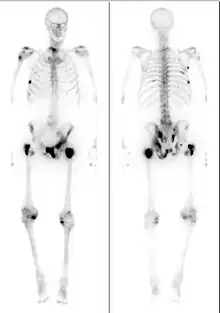

The extent of cancer spread is assessed by MRI or PSMA scan – a positron emission tomography (PET) imaging technique where a radioactive label that binds the prostate protein prostate-specific membrane antigen is used to detect metastases distant from the prostate.[26][22] CT scans may also be used, but are less able to detect spread outside the prostate than MRI. Bone scintigraphy is used to test for spread of cancer to bones.[26]